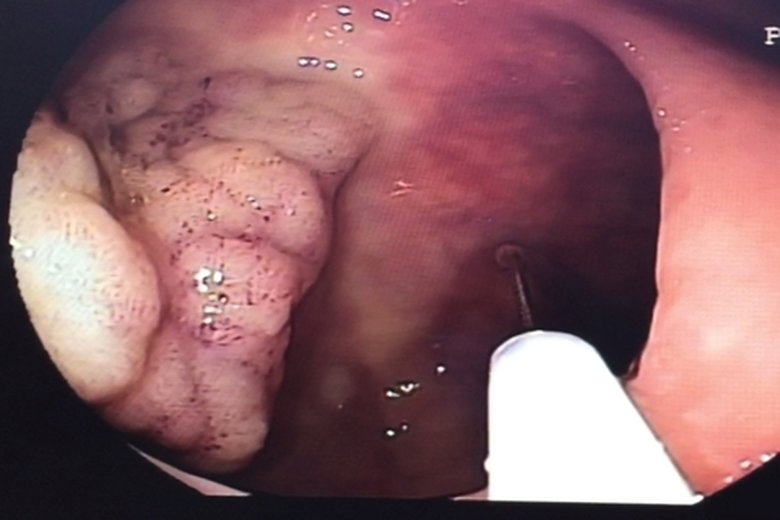

內視鏡切除瘜肉免動刀

醫生操作時將一根導管與攝像儀探入大腸內,以查看大腸內部的狀況。圖為內視鏡光源照射瘜肉組織外觀(衛福部朴子醫院提供)

【新唐人亞太台 2015 年 12 月 11 日訊】家族有患大腸瘜肉,或家族史患有大腸癌或線性瘜肉,是罹患大腸癌的高危險群。大腸瘜肉演變為大腸癌之前症狀不明顯,除非瘜肉已經大於1公分或已到晚期才會出現不適的症狀。大腸內視鏡做檢查,可早期發現大腸性瘜肉並切除,有效降低大腸癌的發生率。